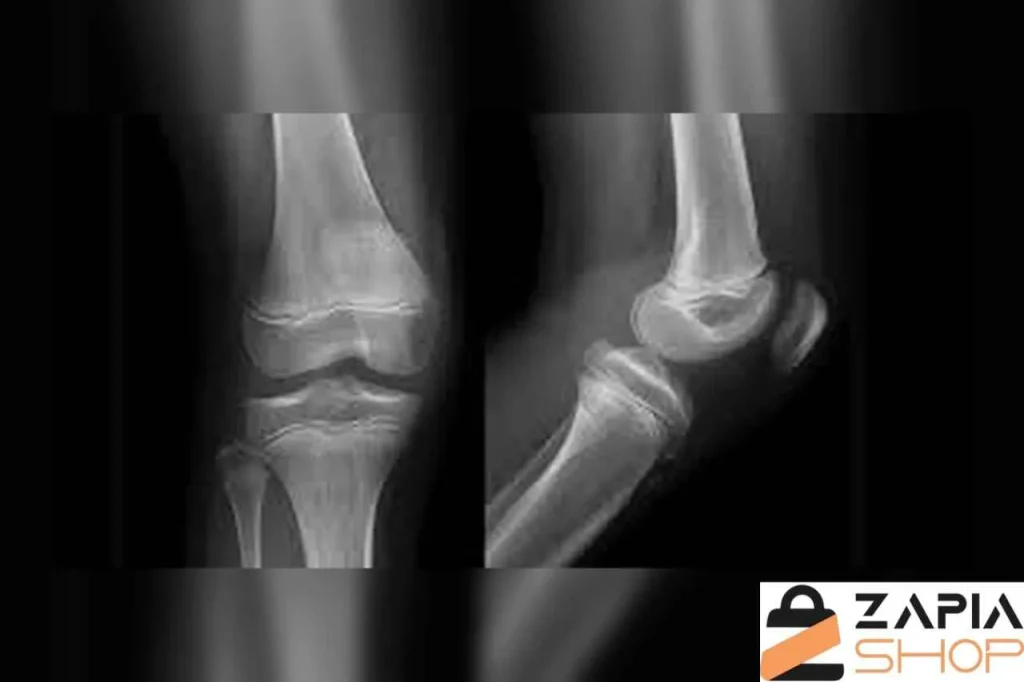

تصویربرداری

در برخی موارد، برای بررسی دقیقتر وضعیت مفصل و تشخیص شدت عقب زدگی زانو، پزشک از روشهای تصویربرداری استفاده میکند. رادیوگرافی ساده میتواند زاویه بین استخوان ران و درشتنی را در حالت ایستاده نشان دهد و مشخص کند که آیا هایپراکستنشن از نوع استخوانی است یا فقط به دلیل ضعف عضلانی اتفاق میافتد.

در موارد پیچیدهتر، MRI نیز ممکن است برای ارزیابی سلامت رباطها (بهویژه ACL) و بافت نرم اطراف زانو تجویز شود.

تصویربرداری به پزشک کمک میکند تا:

- زاویه دقیق رکورواتوم زانو را اندازهگیری کند.

- آسیب یا کشیدگی رباط صلیبی قدامی (ACL) را بررسی کند.

- تغییرات احتمالی روی سطوح غضروفی مفصل را شناسایی کند.

- برنامه درمانی دقیقتری برای بیمار تنظیم کند.